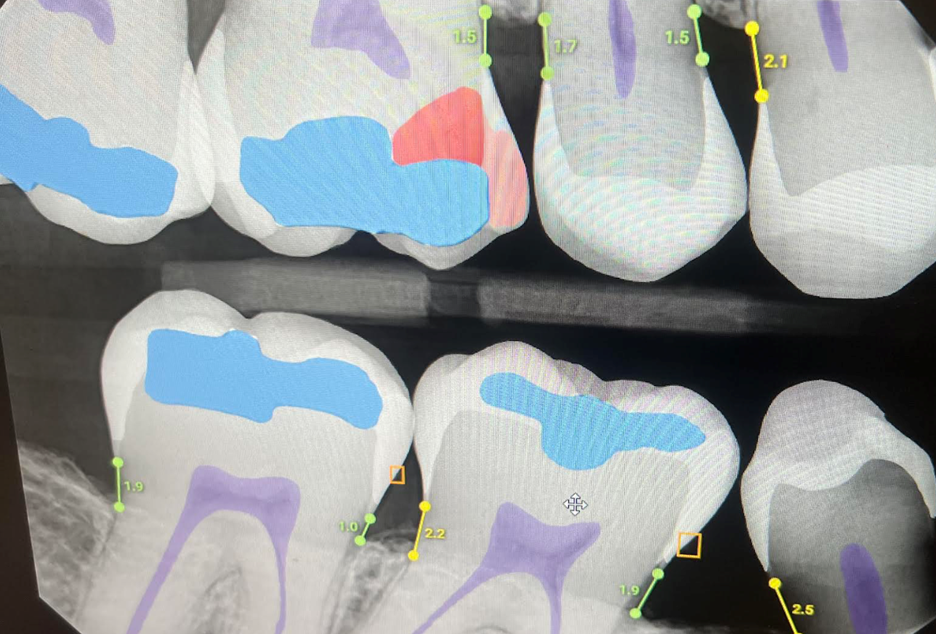

With viewing under Overjet this makes it easy for the hygienist to see, the patient to see, the doctor to see, and also easy to explain to the patient:

Now that you have no confusion to the patient and they are clearly able to see the red on the screen (which, maybe I should take offense, they seem to trust more than us!) you need to decide whether to do a large MOL composite or a crown (and also convince the patient of the best treatment even if they are on a tight budget). But with Overjet it becomes very objective as to what to do, easier to convince the patient, with no worry about insurance denial:

That’s right – it shows you the percentage of the tooth that is decayed. 55% of decay is a clear indication for a crown, making this a very straightforward treatment decision with no second guessing. This percentage is also great to track smaller lesions that are being “watched” where you can see if they are growing between appointments and need to be treated.